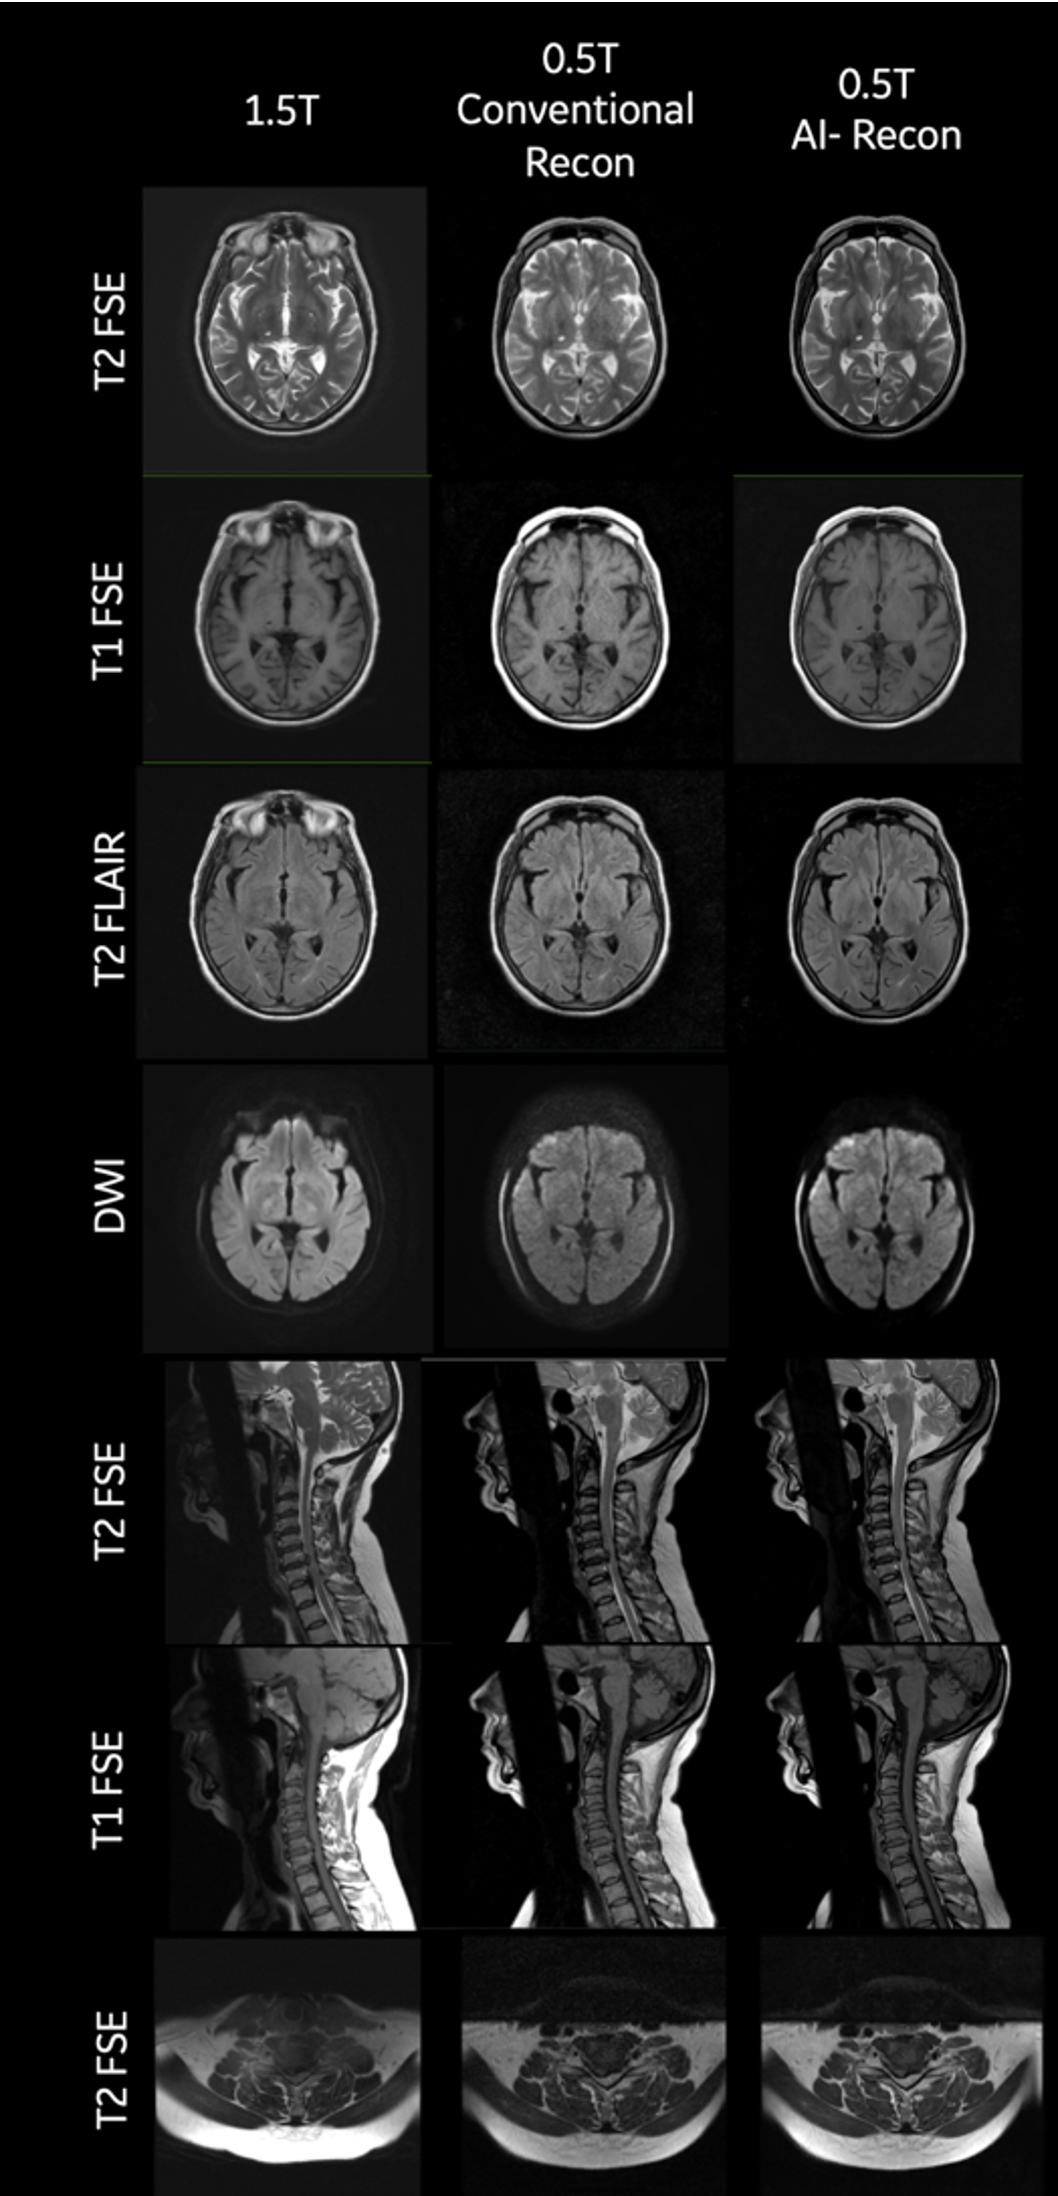

A total of 210 series (excluding localizers) were obtained from 65 patients. Typical images are shown in Figure 1. AI reconstructed DICOM series were rated for image quality by 2-3 radiologists. Out of the 210 series, 190 series were above diagnostic level (Likert score > 5) and only 20 series were rated below diagnostic level. Likert rating over 210 series had an average of 6.27 ± 1.19. The average distribution of ratings of radiologists are shown in figure 2 and per contrast is shown in Table 3. There was very low inter-rater variability among radiologists on image quality rating: inter-rator ratings difference was 1.73 ± 1.12. Of the 20 series rated below diagnostic image quality, 5 were due to excessive motion artifacts, 2 were due to RF interference noise, 7 were poor quality brain SWAN images, 6 were poor quality c-spine images due to CSF pulsation artefacts.Wilcoxon paired signed rank test between AI reconstructed images and non-AI reconstructed images showed statistically significant IQ improvement (5.3 ± 1.38 vs. 7.3 ± 1.65, p<5e-14).

Figure 1: Typical images from the 0.5T scanner for head and C-Spine and the corresponding 1.5T Creator image from the same patient.